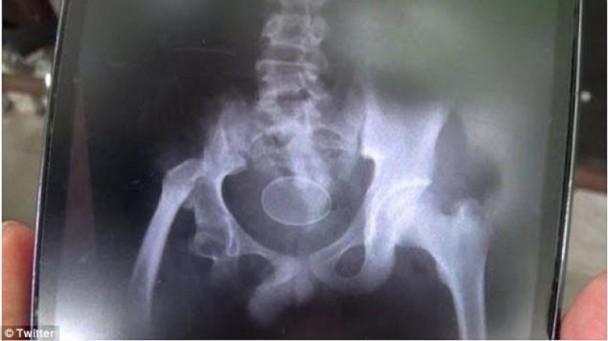

来自印尼的一名14岁男童,2年前被发现会“生蛋”,长久以来已生下20个球形物体,而且每个球体内的物质永远都全是“蛋白”或“蛋黄”。虽然不少医生对他能生蛋的情况存疑,但他最近又在医生面前排出类似鸡蛋的物体,令众人摸不着头脑。

据港媒援引《每日邮报》报道,来自南苏拉威西省的阿克马尔(Akmal),自2016年来不断从体内排出多颗类似鸡蛋的物体,近日又再排出2颗球体。阿克马尔的父亲表示,自己亲手打破球体后,发现里面全是黄色物体。

报道称,负责治疗阿克马尔的医院发言人表示,纵然他们未有亲眼看见,但怀疑这些鸡蛋是被故意推入阿克马尔的直肠。但其父亲立即否认道:“他从来没有吞下整只鸡蛋,为什么他会那样做?”团队现在仍在研究阿克马尔的情况。